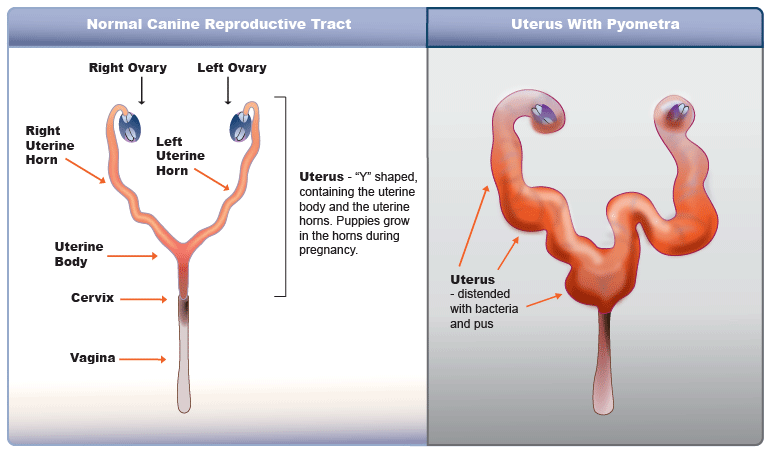

개의 자궁 축농증

자궁축농증은 자궁내 감염이 일어나 농성 물질이 배출되지 않고 자궁 내에 고름이 축적되는 질환으로 반드시 외과적으로 치료해야 하는 질환입니다.중성화하지 않은 여자아이가 갑자기 식욕부진을 보이면서 물을 많이 마시려면 한번쯤은 이 질환을 의심해 봐야 해요.